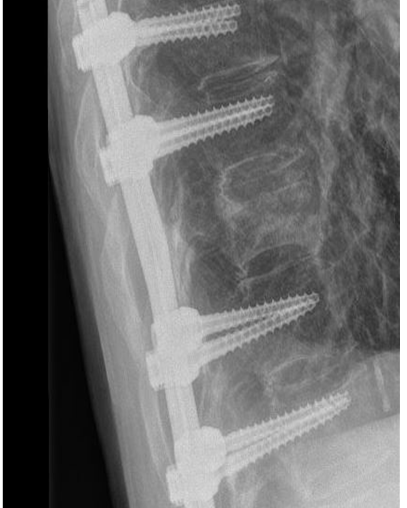

Bij een instabiele breuk is dit risico wel aanwezig en daarom is een stabiliserende operatie noodzakelijk. De revalidatie zal grotendeels overeenkomen met de revalidatie na een stabiele breuk zonder operatie.

Controle polikliniek

Na 12 weken komt u voor controle in de polikliniek bij uw behandelend arts. Er wordt een röntgenfoto gemaakt van uw rug en de voortgang van het herstel wordt beoordeeld. U krijgt advies over de opbouw van de oefeningen en hoe om te gaan met uw rug tijdens dagelijkse activiteiten. Het advies is om de coördinatie en de kracht van uw rugspieren, buik- en flankspieren te trainen. Meestal wordt u hiervoor verwezen naar een fysiotherapeut.